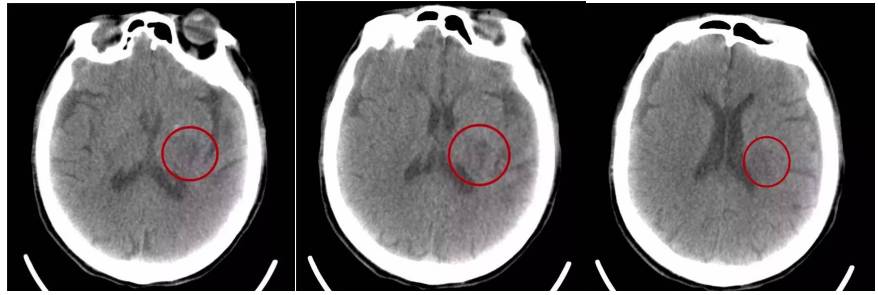

急诊室脑梗塞移动CT床旁脑部扫描

脑科ICU脑出血移动CT床旁脑部扫描

脑科手术室脑损伤移动CT床旁脑部扫描